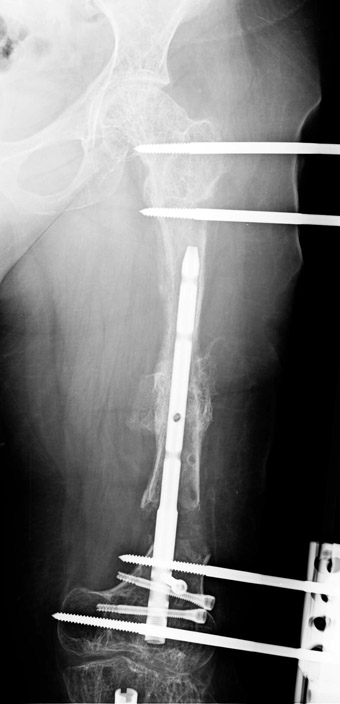

Kırık kaynama yokluklannın tedavisi hala, ortopedik cerrah için çözümü güç sorunlardandır. Tek bir tedavi yöntemi yoktur. Tüm bu yöntemler problemli ve daima komplikasyonlara açıktır. Kaynamamaya enfeksiyon, yumuşak doku kaybı ile deformite ve kısalık eşlik edebilmektedir, Kaynamama için internal ve eksternal birçok teknik belirtilmiştir. Kaynamayan kemik uçlarının çıkartılması, damarlı fibula veya fibula grefti, damarlı kas greftleri ile birlikte internal fiksasyon uygulamaları, elektrik stimulasyon gibi uygulamalar kaynamamada bir şeçenektir. Fakat kısalık ve deformite gibi ek patolojiler tedavisinde kısıtlı kalmaktadır. İlizarov eksternal fiksatörü ile uygulanan distraksiyon osteogenezi uygulamaları ile birlikte yapılan psödoartroz sahasından akut kısatma ve aynı kemikteki diğer segmentten uzatma yapılmaktadır. Ilizarov ve arkadasları, kendi geliştirdikleri yöntem ve fiksatörle, aynı anda, hastanın günlük aktivitelerini kısıtlamadan, eklem fonksiyonlarını koruyarak kaynamayı basarmıs,deformiteyi düzeltmis, uzunlugu yeniden sağlamıstır. Bu teknik sayesinde kemik defektlerinin kapatılması ve enfeksiyon gibi hastaya morbidite getiren ek patolojiler giderilmiş aynı zamanda kısalıkta telafi edilmiştir.